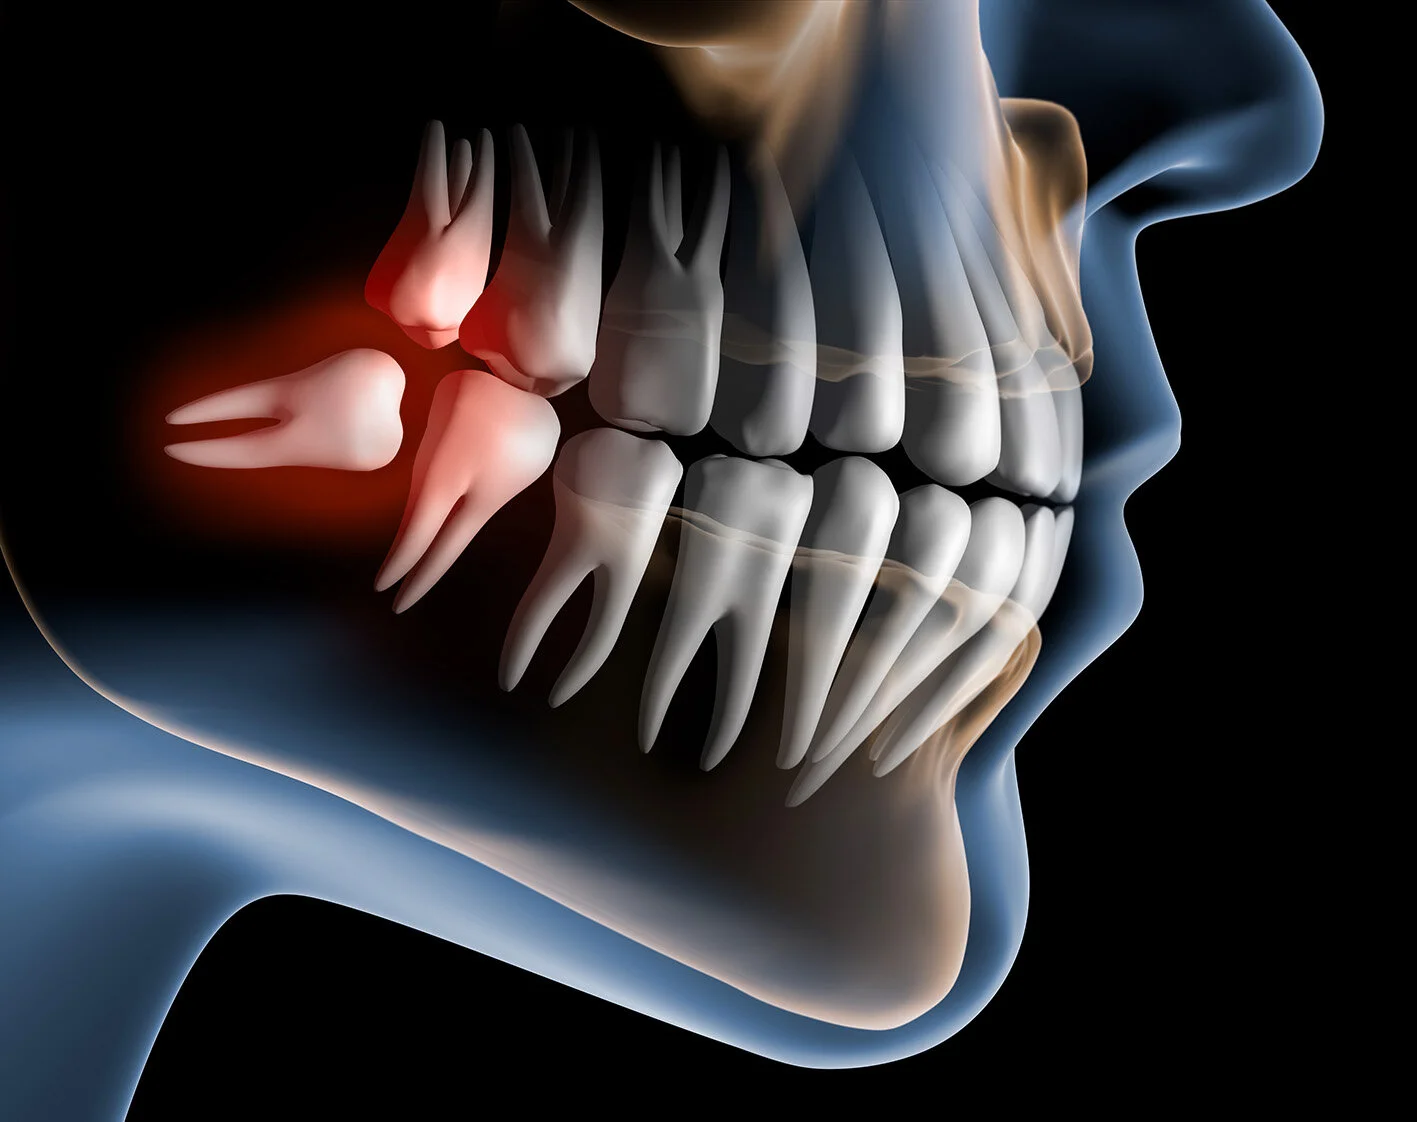

Do Sydney patients need time off work or school after wisdom tooth extraction?

Most people need about a week away from regular activities. Teenagers often schedule surgery during school holidays, while university students and young professionals choose quieter times in their schedule to allow recovery. The amount of time required depends on the complexity of surgery and individual healing.

Is wisdom tooth removal different in Sydney compared to other areas?

The procedure itself is the same, but Sydney patients benefit from access to Oral & Maxillofacial Surgeons who regularly perform complex extractions in hospital and clinical settings. Having two clinics one in Bondi Junction and one in Lindfield — provides convenient access for patients across the Eastern Suburbs and North Shore.